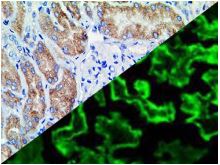

Bio SB has developed a highly sensitive Immunofluorescence and non-biotin monovalent Fab micropolymer IHC detection systems for the detection of IVD antibodies for Complement (C1q, C3c, C3d, C4c, C4d), Serum Proteins (Albumin and Fibrinogen) and Immunoglobulins (IgA, IgD, IgE, IgG, IgM, Kappa and Lambda) related to autoimmune conditions. Our innovative IF and IHC detection systems and high affinity antibodies, have opened the doors for a faster and accurate Immunofluorescence and Immunohistochemistry applicable to Autoimmune Disease like Nephropathies and Lupus.

These antibodies and detection systems are intended for use in Immunohistochemical (IHC) and Immunofluorescence (IF) applications of formalin-fixed paraffin-embedded tissues (FFPE), frozen tissue sections and cell preparations.